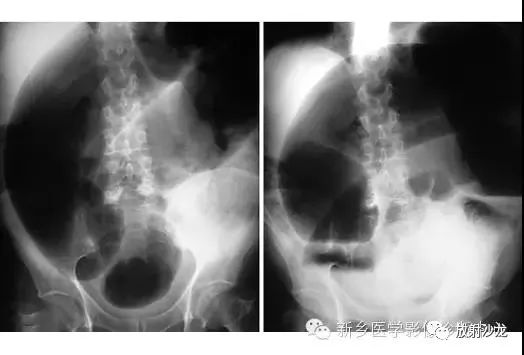

上图腹部平片检查是一6岁男孩,出现呕吐和急性右髂窝疼痛进行的。两个关键的发现在哪里?(提示:通过放射科医生所提供的箭头可以缩小关注点。)

右髂窝多个扩张的小肠襻出现小的钙化结节。小肠袢可与大肠区分开来,因为小肠的环状襞延伸至整个肠壁,而结肠袋只是部分延伸存在。在右下腹(箭头)的钙化结节高度提示阑尾粘连。这个病人开腹手术发现阑尾粘连致小肠梗阻。